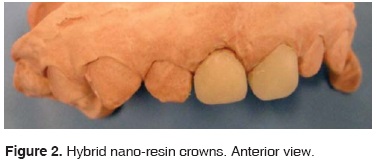

During the first visit, impressions were taken with irreversible hydrocolloid; and over the model teeth were carved with a 169 L bur, 1 mm were eroded at all sides, rounded borders without retention and shaping a cervical chamfer. The model was then sent to the laboratory in order to manufacture crowns, with shape and color specifications (Figures 2 and 3).